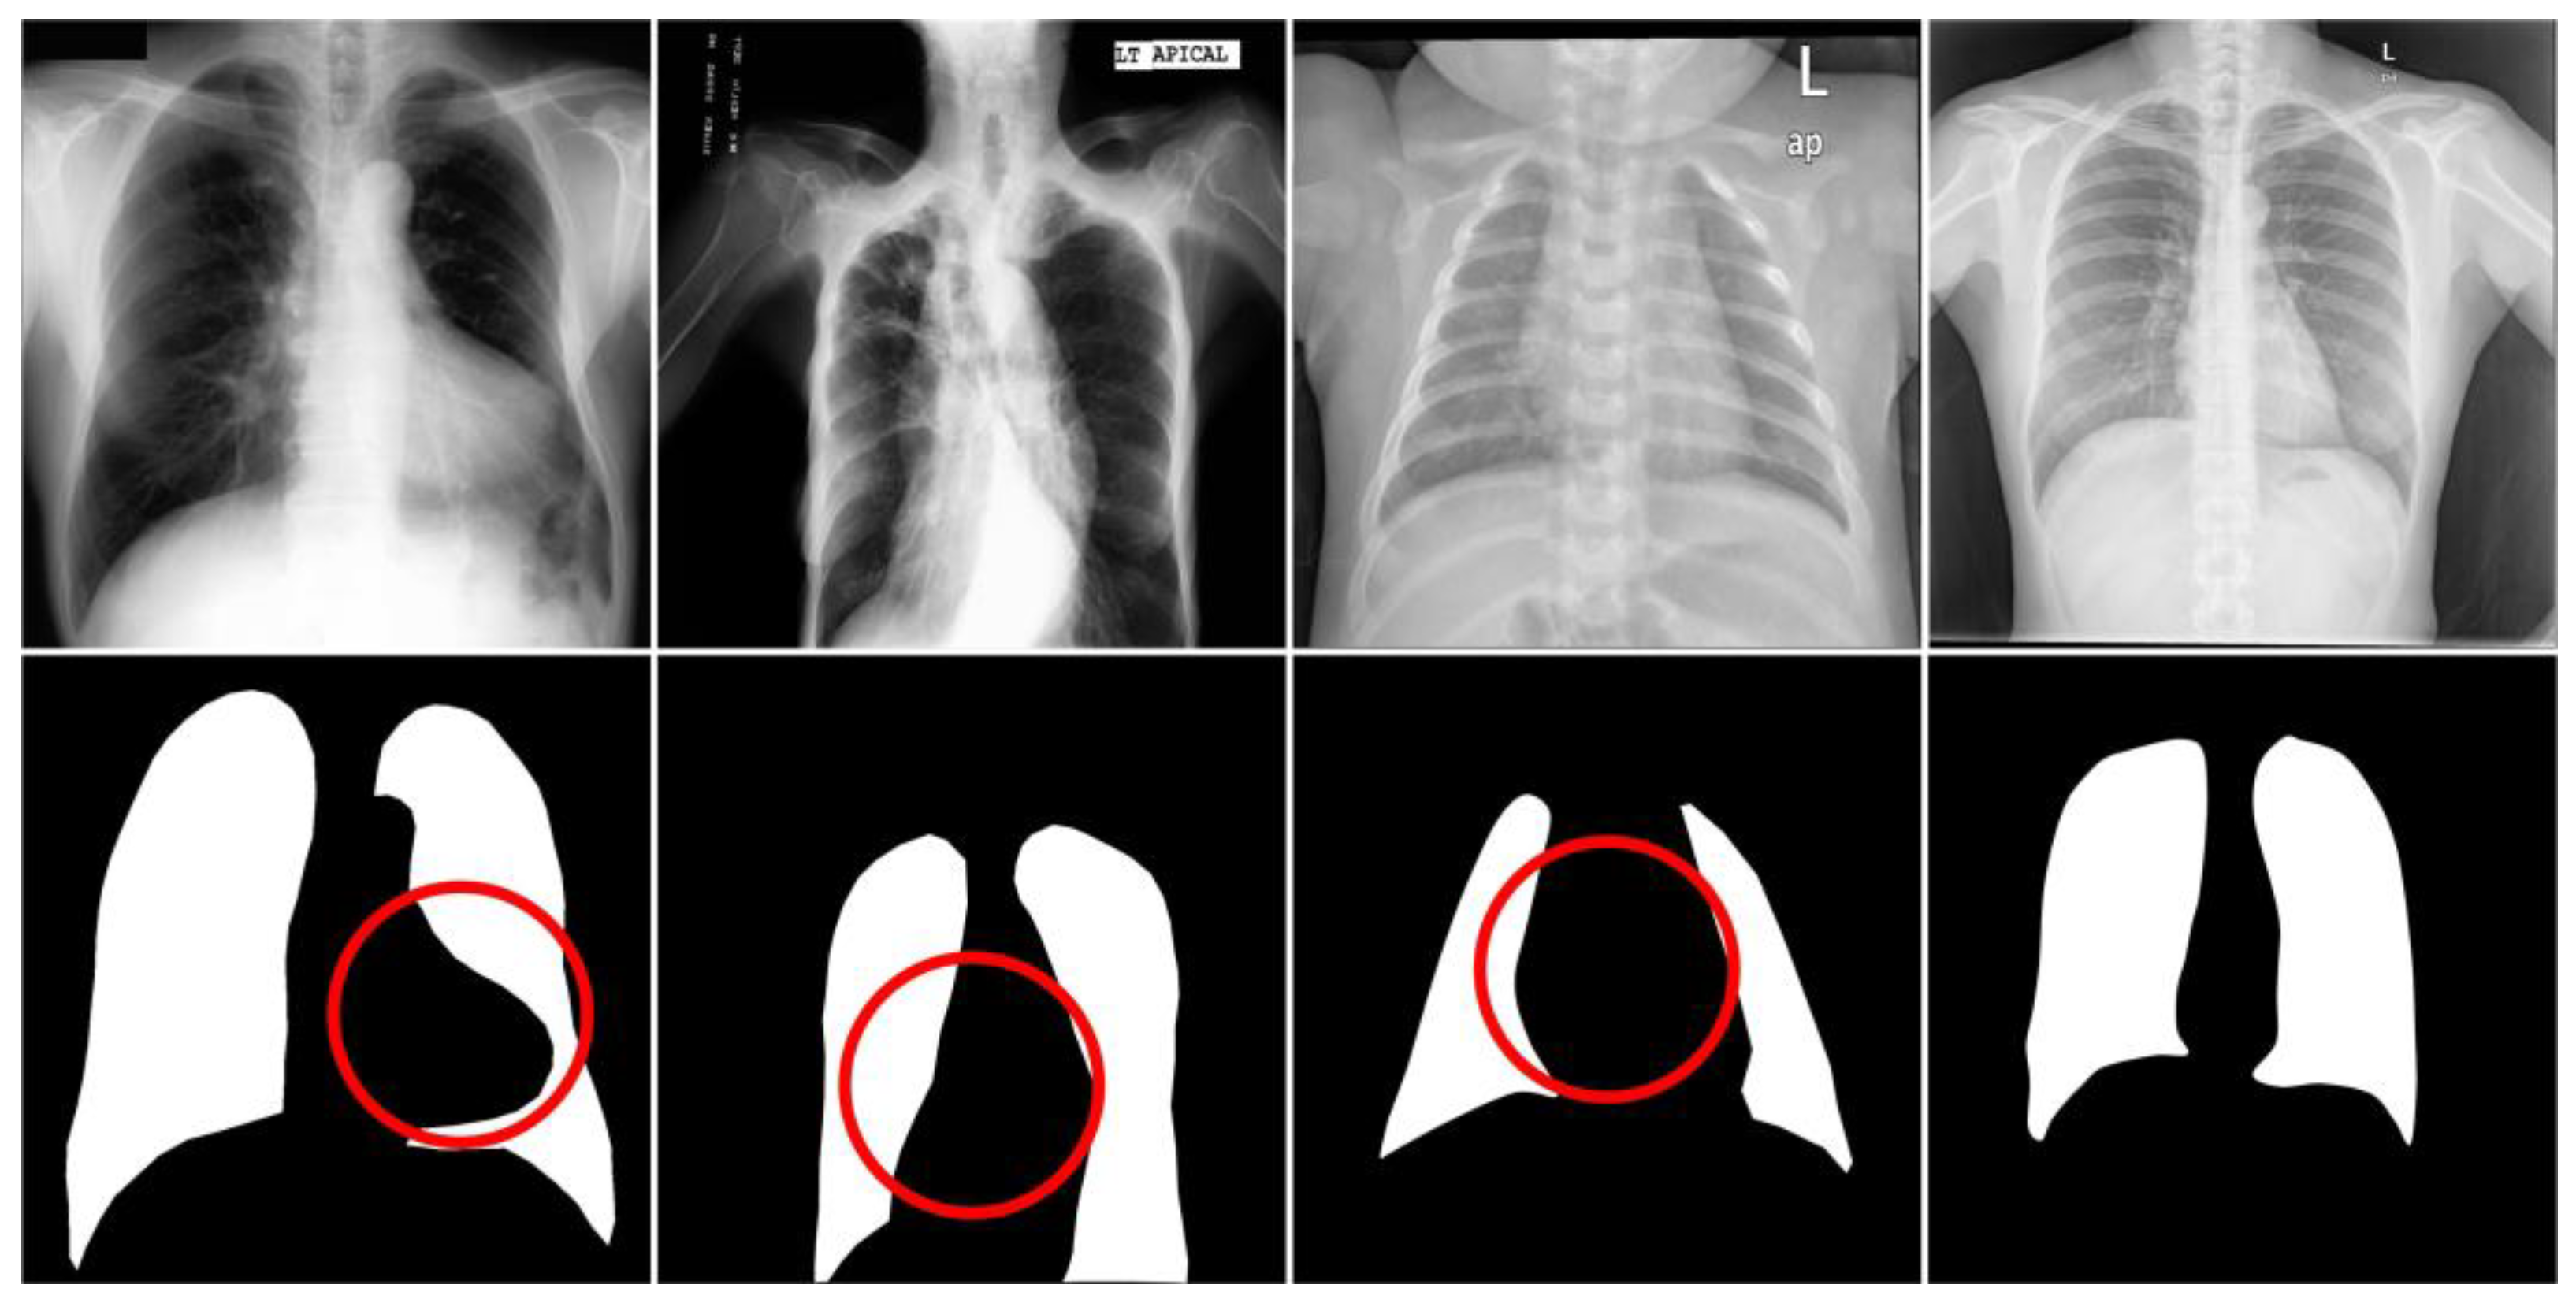

Figure 3.

Images and masks of the JSRT dataset.